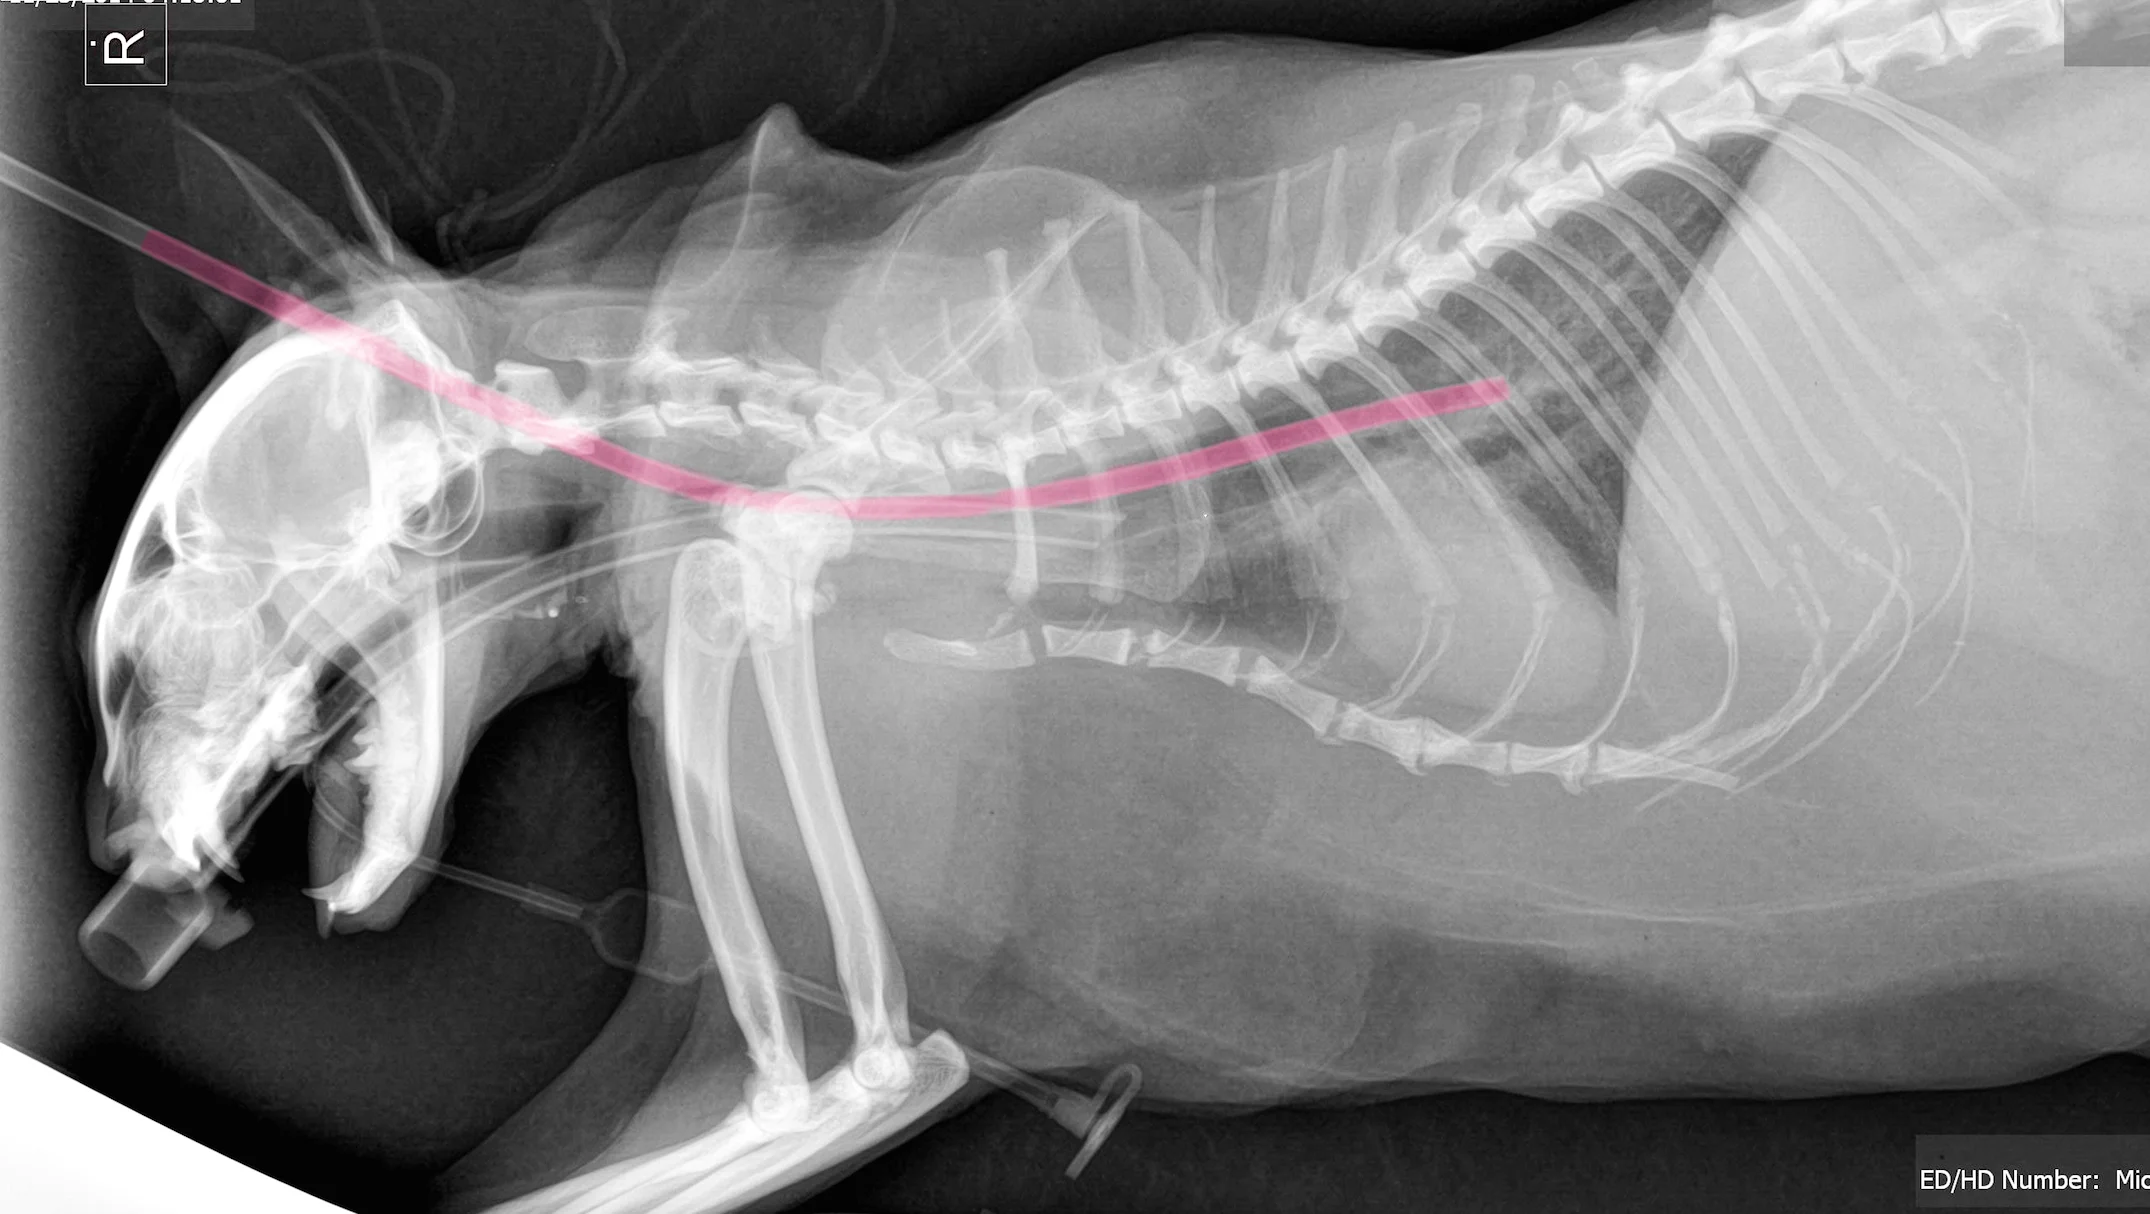

Esophagostomy feeding tube placement in the dog and cat. This tube enters the esophagus the food pipe from a surgical incision on the left side of the neck. Esophagostomy feeding tube placement in the dog and cat J Vet Dent.

Fewer complications than with pharyngostomy tubes. Von Werthrern C J Wess G 2001 A new technique for insertion of esophagostomy. Your pet has had a type of feeding tube called an esophagostomy tube E-tube placed.

Use a different technique such as a gastrostomy tube. Surgical placement of an esophagostomy feeding tube e-tube in a cat. Unlike gastrostomy tubes Gastrostomy.

With a J-tube food bypasses the stomach and enters directly in to the small intestine. Cat feeding tube placement. The left lateral and ventral cervical area should be clipped and an aseptic preparation performed.